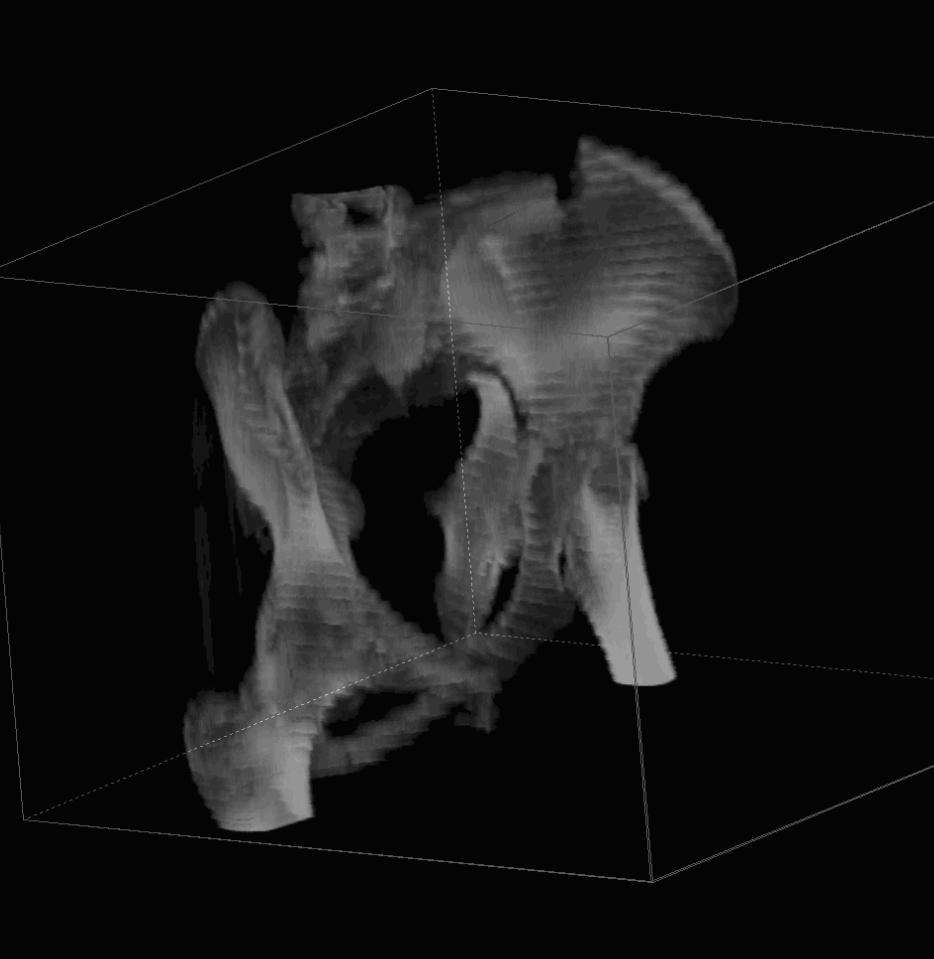

Уважаемые коллеги! С прошедшеми Вас праздниками. Теперь ближе к трудовым будням. Поступила 16 летняя девушка неделю назад. Механизм травмы падение с 5 этажа. Краткий диагноз:закрытый перелом левой ключицы, левого плеча, закрытый вертикально и ротационно нестабильный перелом костей таза:закрытый перелом левой подвздошной кости, переломы лонной кости справа, перелом обоих колонн вертлужной впадины слева;субкапитальный перелом шейки левой бедренной кости со смещением. По тактике лечения таза возникли следующие вопросы: 1. С чего начать - фиксации переломов вертлужной впадины или устранения деформаций таза? 2. Надо ли фиксировать шейку или фиксировать бедро в аппарате вместе с тазом, а после сращения таза планировать ТЭП ТБС? Если имеются еще какие подводные камни, будем рады выслушать.Спасибо.

На снимке ацетабулума редко встречающийся очень низкий перелом, наверное, трудно было репозицию через один доступ? Перелом как бы замкнулся в квадрилатеральной поврехности.